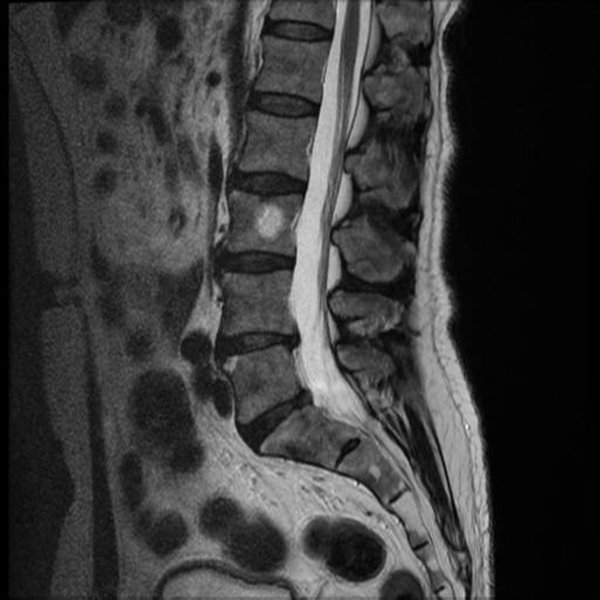

MRI showing disc protrusion compressing an L5 nerve root

MRI demonstrating a lumbar disc protrusion impinging on a nerve root.